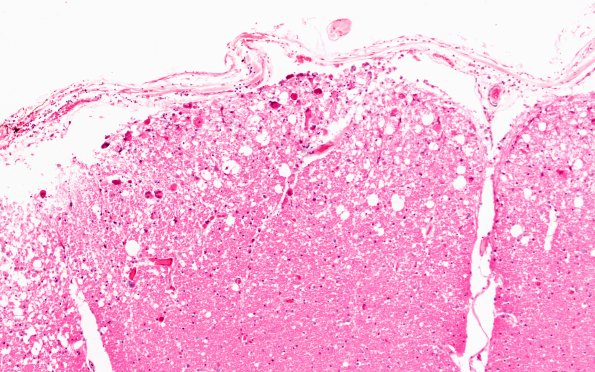

2E3 CMV (Case 2) Spinal cord rim

2E3-5 Other spinal cord sections showing numerous subpial areas of CMV myelitis. (H&E)